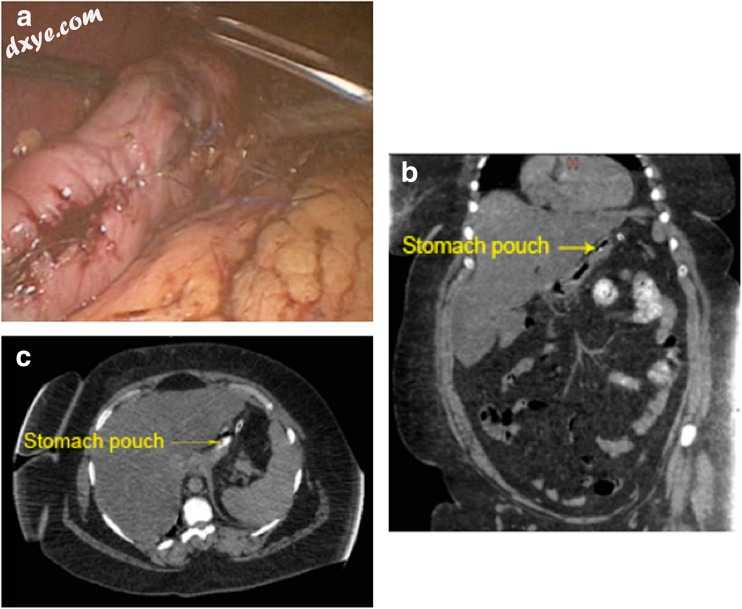

图4

程序结束时的全局视图。术后CT扫描与口腔对比(b轴和c冠状视图)

用稀释的亚甲蓝进行泄漏试验,并将管排放在胃袋附近[8]。由于早期渗漏通常表现出微妙的症状[7],因此本系列中常规采用口腔对比的术后计算机断层扫描(CT)(术后30-48小时),以验证没有泄漏并证明适当大小的小袋(图4b,c)。

该病例系列研究了三名中年女性(中位年龄42岁;范围39-51岁)患有超级肥胖(中位体重指数(BMI)50 kg / m2;范围49-53 kg / m2)(表(表1)0.1)。患者B和C具有相似的共病概况,除了患者B曾进行过腹部手术,患者C患有高血压(HTN)。然而,患者A患有阻塞性睡眠呼吸暂停(OSA),高血压,复发性切口疝,以及先前的网状腹部手术。没有患者患有糖尿病或裂孔疝(表1).1)。中位手术时间为132分钟(范围120-195分钟)(表(表1).1)。手术后,所有患者在医院停留2天,术后常规(30-48小时)CT均无渗漏(表1)。 6个月时中位数超重(EWL)为39%(范围32-43%),1年时为57.7%(范围50.4-63%)。延迟渗漏(手术后7-10天) - 可归因于胃壁的与热相关的脱落 - 在初始随访期间被排除在临床基础上,延长至手术后30天。

在作者有限的病例系列中,作者常规进行口腔对比CT扫描以检测任何泄漏。作者承认,这种额外成像的成本增加了作者无钉技术的成本;但是,作者认为在作者的最初系列中有理由持怀疑态度。虽然作者的患者密切监测早期泄漏的临床症状,如心动过速,发热和不相等的吸气[7],但作者注意到这些迹象并非泄漏特异性,可能表明肺不张,这被认为是肥胖症中最常见的并发症。患者[32]。脱水也会导致低度发热和心动过速,并可能使早期泄漏的诊断混乱。作者发现作者的患者很容易脱水,因为术后恶心和呕吐是一个常见的事件。在作者的研究中进行CT扫描的另一个原因是评估小袋的几何形状。